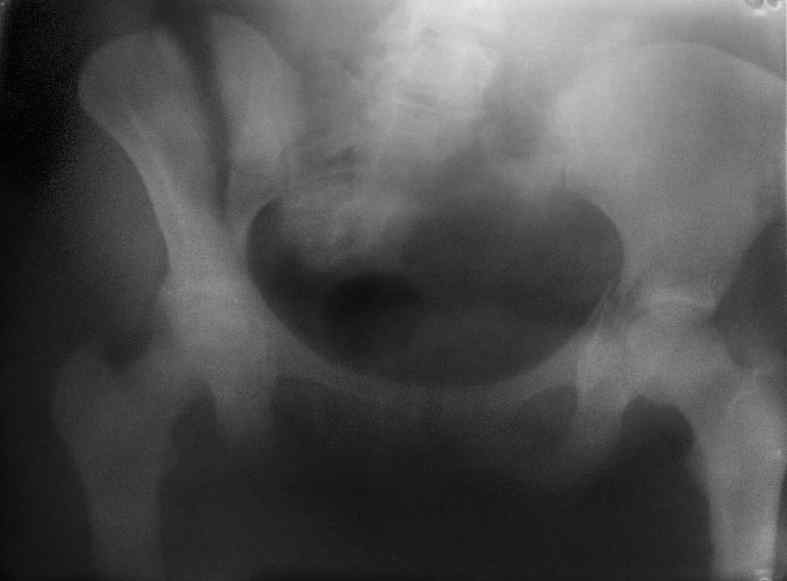

Молодая девушка 19 лет, травма 1 год назад, тогда же прооперирована.

В приложении снимки при поступлении и послеоперационные год назад.